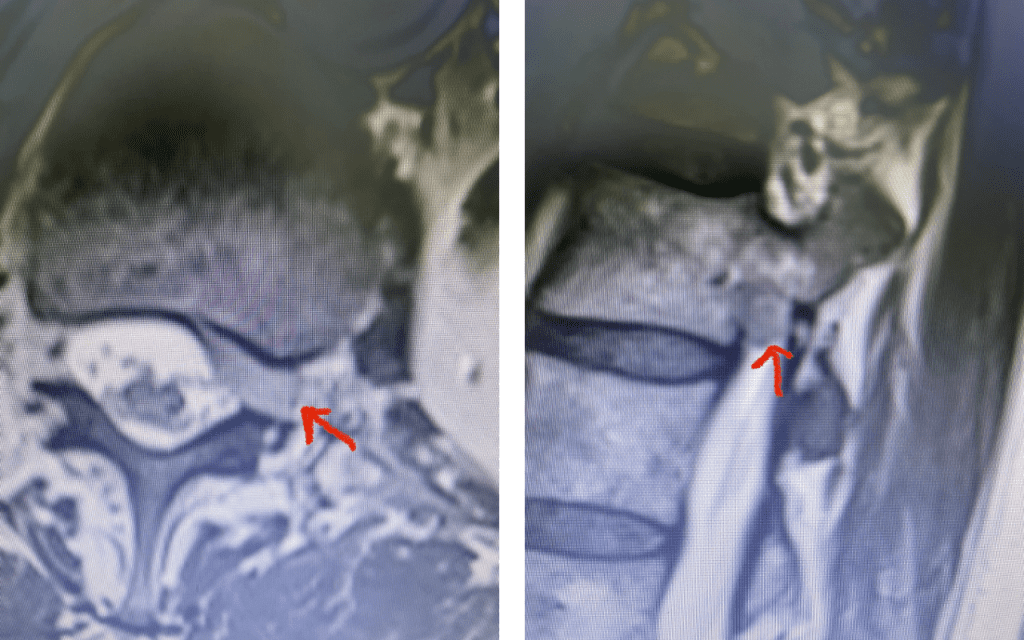

Fig 9: Axial and Sagittal T2-weighted lumbar MRI demonstrating left L4-5 far lateral disc herniation (red arrow). Notice how on the sagittal MRI the disc herniation fills the foramen and is superiorly oriented, compressing the left L4 nerve root against the L4 pedicle (blue arrow).